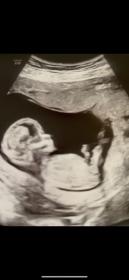

These are from my NT scan at 12 weeks 6 days but I was measuring (and have been) later at 13 weeks 3 days.

I’m driving myself crazy with this one. Do you guys see a nub??